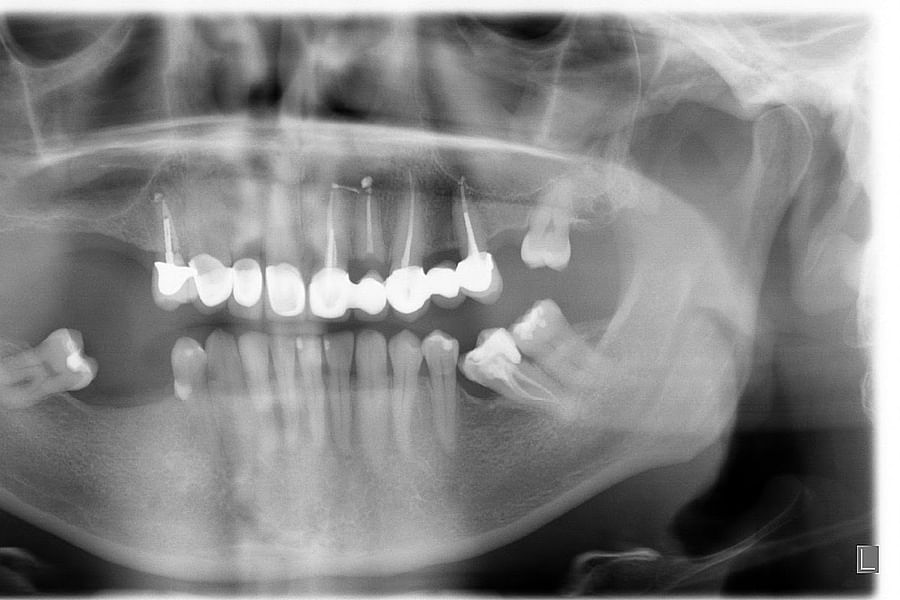

Dental X-rays are more than just tools for diagnosing cavities; they provide a comprehensive view of your oral health status. By allowing dentists to detect problems before they become severe, these images can save patients time, money, and discomfort in the long run. Early detection through modern imaging technology can reveal hidden decay between teeth, bone loss due to gum disease, or even cysts and tumors that are not visible during a standard exam.

- Impacted Teeth - Revealing teeth that are not properly erupting, such as wisdom teeth.

Beyond diagnosis, regular imaging plays a vital role in treatment planning. Whether you're considering braces or implants or undergoing root canal therapy, precise images enable personalized care tailored to your unique anatomy.

Despite the myths surrounding dental x-rays, they play an integral role in preventative dentistry. X-rays allow dentists to detect issues that are not visible during a standard oral exam. This includes early signs of decay between teeth, problems below the gum line, and changes in bone density that could indicate periodontal disease. By identifying these problems early, fundamental dental treatments can be administered promptly, saving patients from more extensive and costly procedures down the line.

Dental x-rays also serve as a critical tool in planning complex dental treatments such as orthodontics, implants, and extractions. The detailed imagery helps create precise treatment plans tailored to each patient's unique anatomy. To explore how modern technology is shaping these plans, visit our page on digital dentistry benefits.